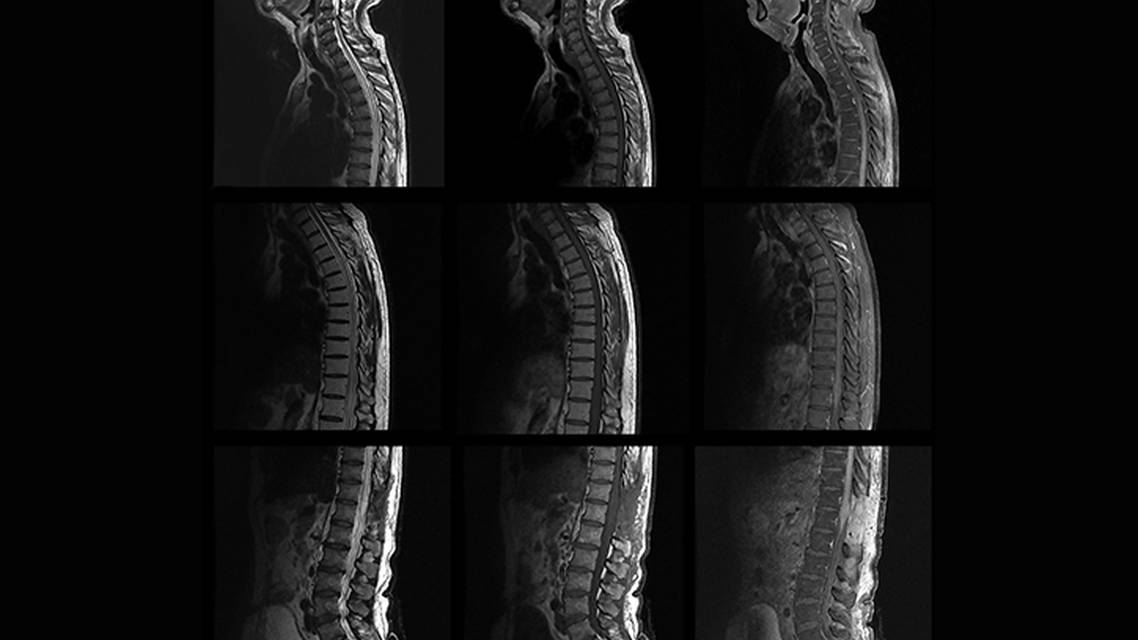

Total spine MRI performed 9 months after JD’s initial presentation showed the lesion had extended to C7 (Figure 1). A fourth DSA now demonstrated a dilated vein near the midline of the cord at L5, warranting further investigation with selective angiography, which discovered an SDAVF at the L5 level, supplied by bilateral L5 branches of the iliolumbar artery (Figure 2).

Characteristic imaging findings of SDAVFs include flow voids, conus swelling (90% of cases), and the “missing piece sign,” a focal geographic nonenhancing area within a long segment of holocord gadolinium enhancement (43% of cases).3,9,10 Even in those who present with these characteristic imaging findings, however, the median time to diagnosis is 6 months, and the average time to definitive diagnosis is 1 to 3 years.6,11 Spinal angiography is the standard modality to confirm and identify the location of an SDAVF, but this is a time-consuming procedure often complicated by variant anatomy. Smaller branches, as were present in this case, often require selective angiography with additional equipment and clinical expertise. Multidisciplinary communication amongst neuroradiology, neurosurgery, neuroendovascular, and neurology specialists is vital to the diagnosis and treatment of SDAVFs.